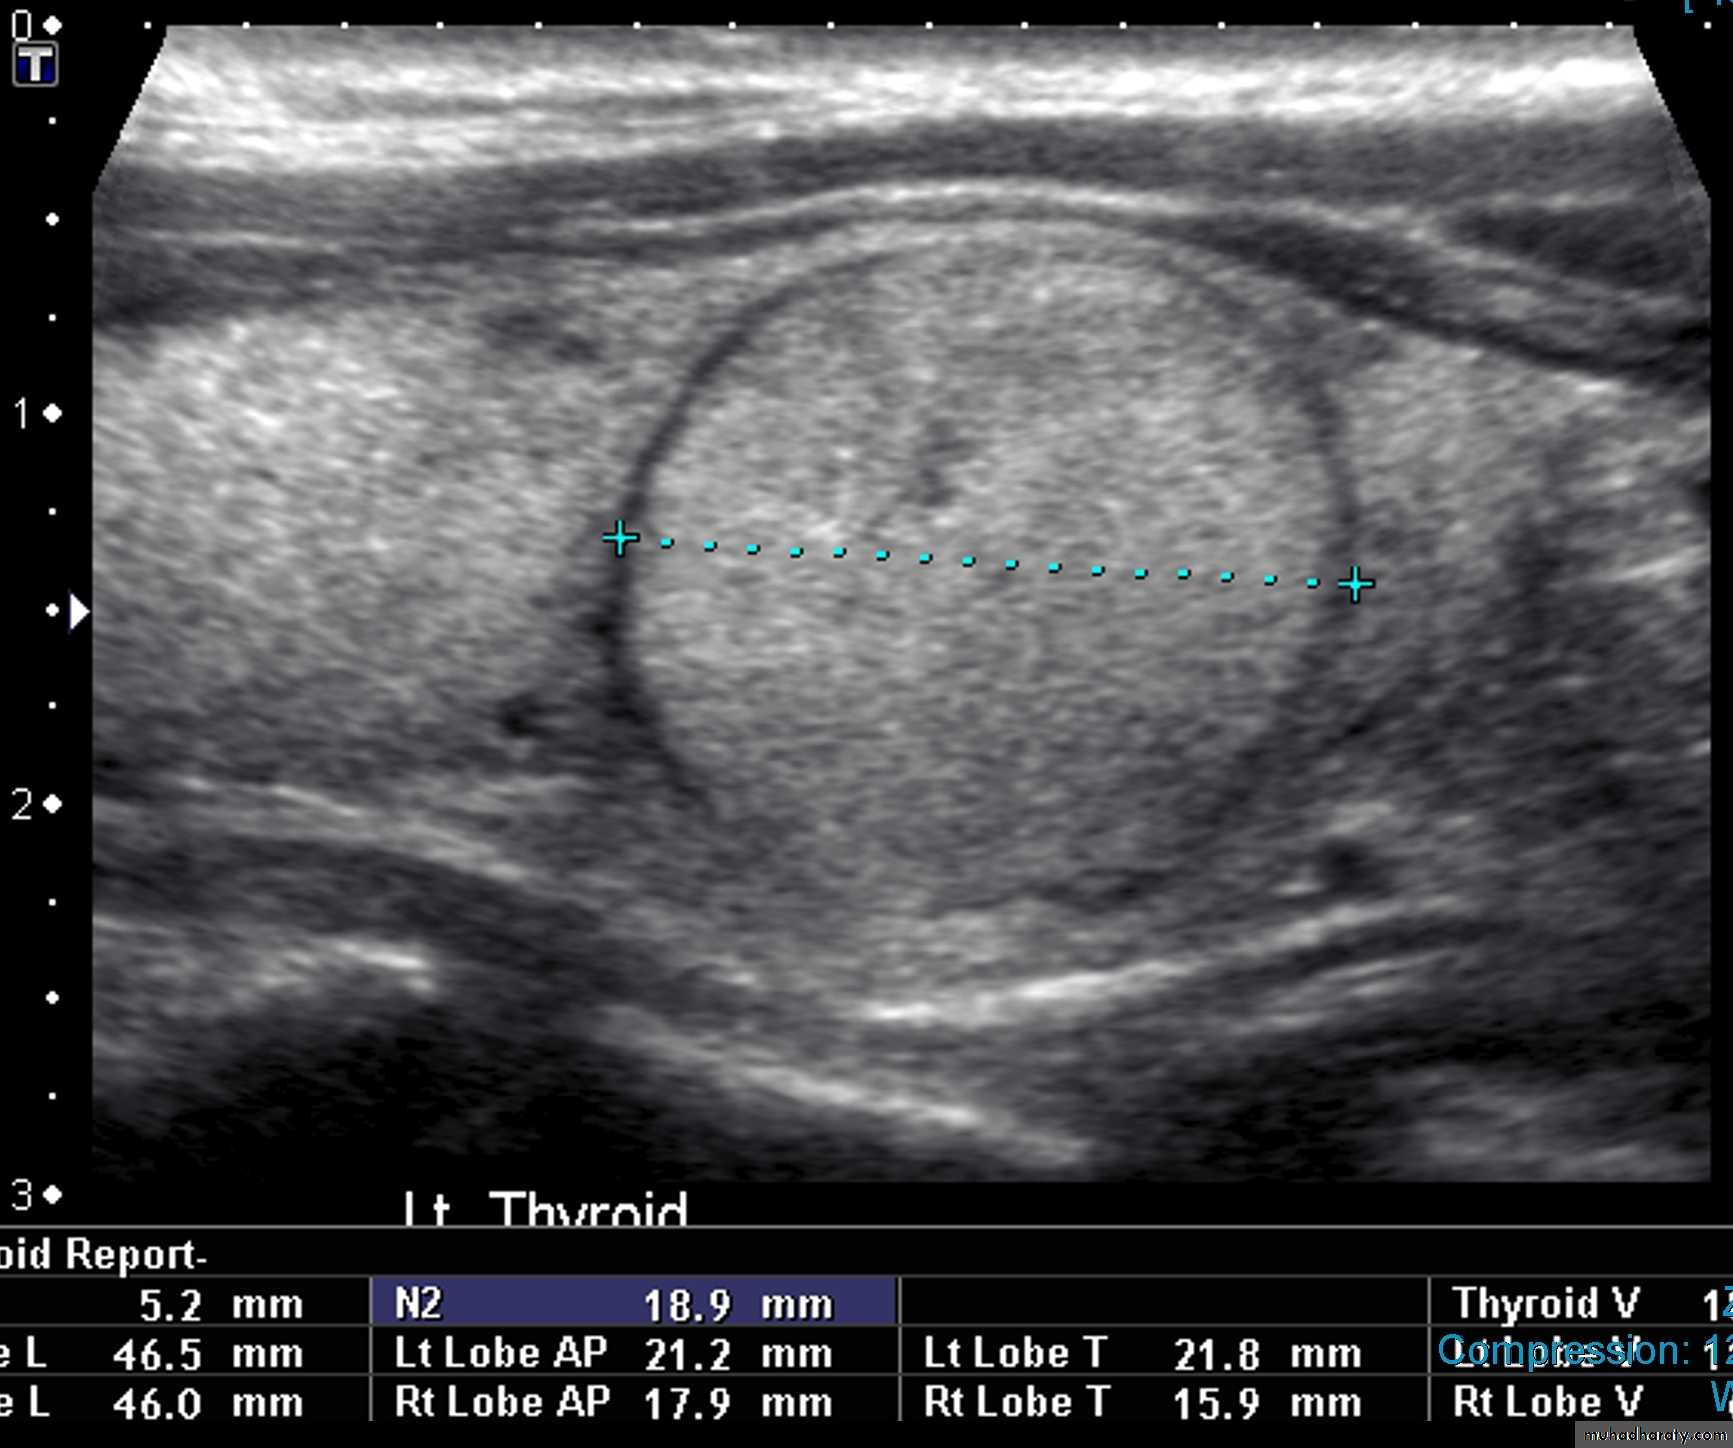

A thyroid nodule is defined as a discrete mass lesion in the thyroid gland, distinguishable from thyroid parenchyma on US.

• Follicular adenoma is a true benign neoplasm of the thyroid gland.

• US is the imaging investigation of choice for characterization of thyroid nodules.

• Features of thyroid nodules assessed with US include:• Size: the incidence of cancer in nodules smaller than 1 cm is extremely low

• Composition: cystic, solid or mixed

• Margins: well-defined margin or ‘halo’; irregular margins